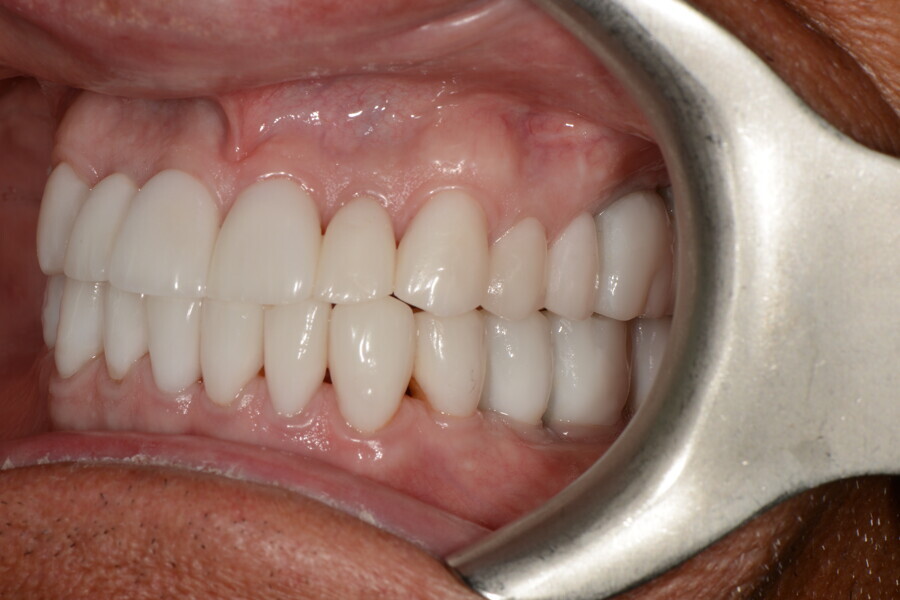

After the first phase of aligner treatment, we had achieved better inter-arch coherence, better maxillary arch expansion, and some space for improving the anterior tooth proportions restoratively (Fig. 19). We then temporarily restored the anterior teeth directly with composite, closing the spaces, improving the tooth proportions and further increasing the maxillary arch expansion (Fig. 20). We used restorative arch expansion to reduce the orthodontic destabilisation of the teeth to achieve the correct inter-arch coherence and retain the teeth in the cortical bone.38 A refinement aligner phase was undertaken to improve the final alignment of the gingival zenith and to improve the inter-arch coherence (Fig. 21). The periods of the first orthodontic phase and of the refinement were used to augment the mandibular and maxillary bone and to place the implants (Fig. 22). At the end of the orthodontic treatment, the case was finalised with ceramic veneers in the anterior area and temporary restorations on the implants in the posterior area (Figs. 23–26).

The provisional phase of about four months was important to allow the peri-implant tissue to mature and to teach the patient to chew correctly with chewing gum, cotton rolls and silicone masticatory sticks. This is fundamental training for the patient to achieve the correct alternating unilateral masticatory cycle needed to obtain the ideal rehabilitation of the masticatory system. We wanted the patient to achieve ideal masticatory and swallowing function. After sufficient rehabilitation time, we finalised the case with posterior zirconia crowns screwed on to the implants (Fig. 27).26

Our ideal final rehabilitation goals were:

• posterior stability;

• inter-arch coherence and U-shaped arches;

• anterior freedom during mastication;

• minimum disclusion vertical dimension;

• alternating unilateral masticatory cycle;

• physiological swallowing and high tongue posture against the palate; and

• mandibular disclusion advancing the mandible freely.